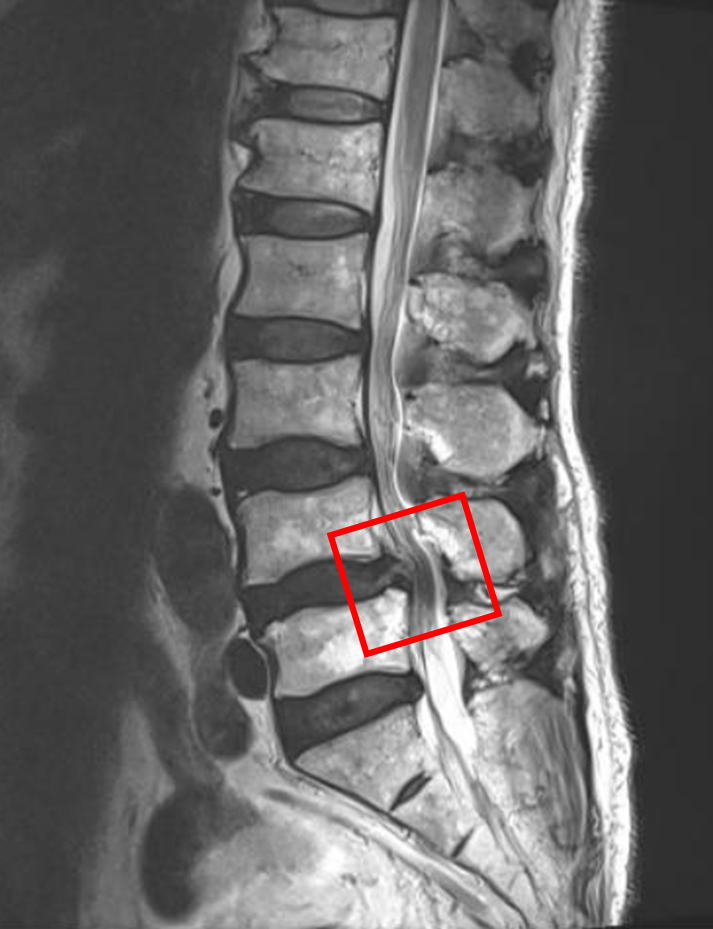

この患者様は赤い枠で示されている箇所(L4/5)に脊柱管狭窄症を認めます。